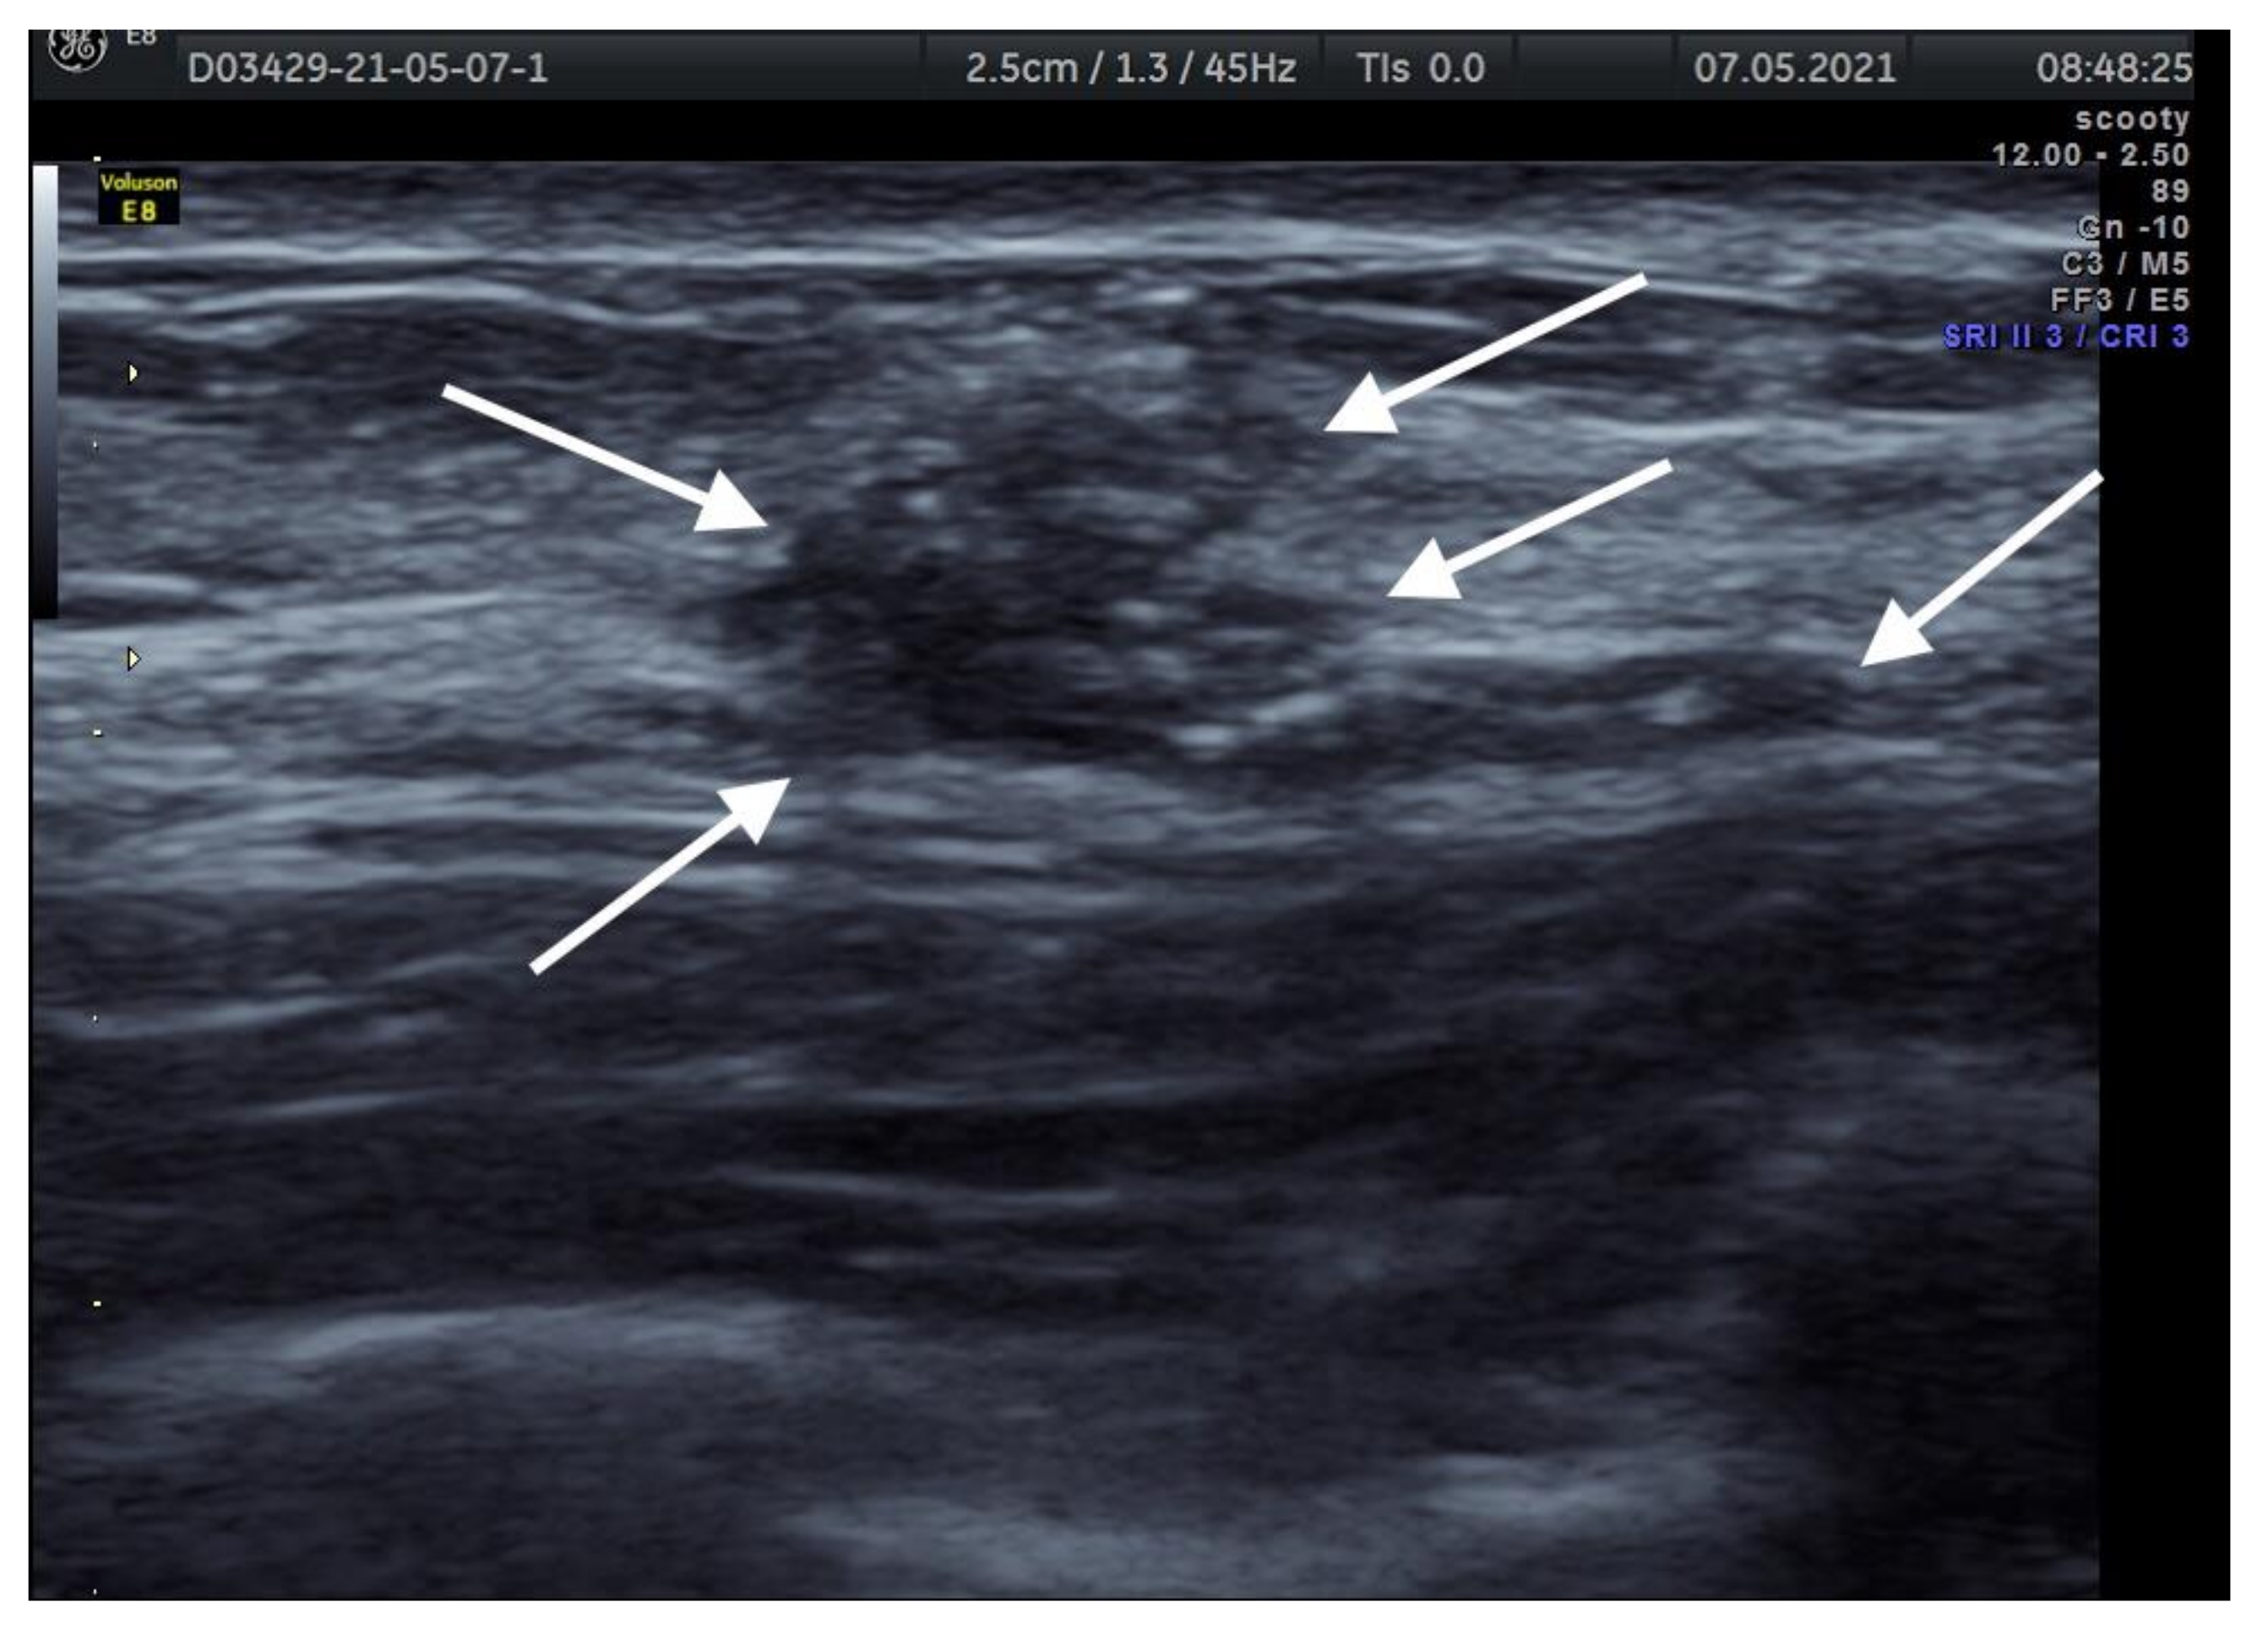

6. Imaging Findings